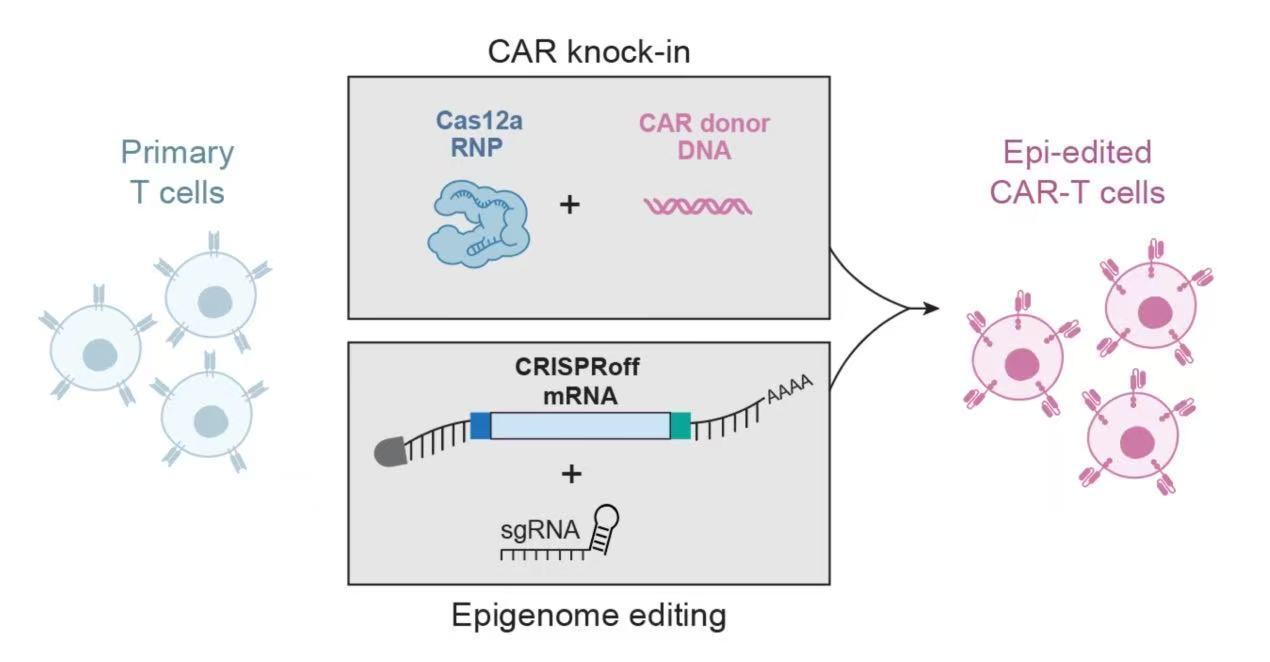

新平臺能同時修改T細(xì)胞中多個基因